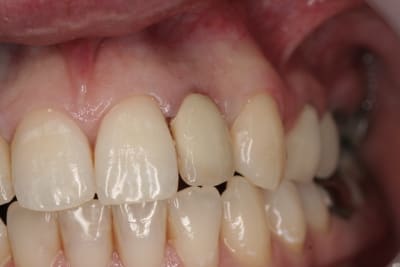

photos finish!!!

à noter...avec le flash...difficile de rendre le "naturel" de ces restaurations(teintes très claires)...après petite gingivoplastie pour harmoniser la hauteur des collets...(surtout pour 12...)